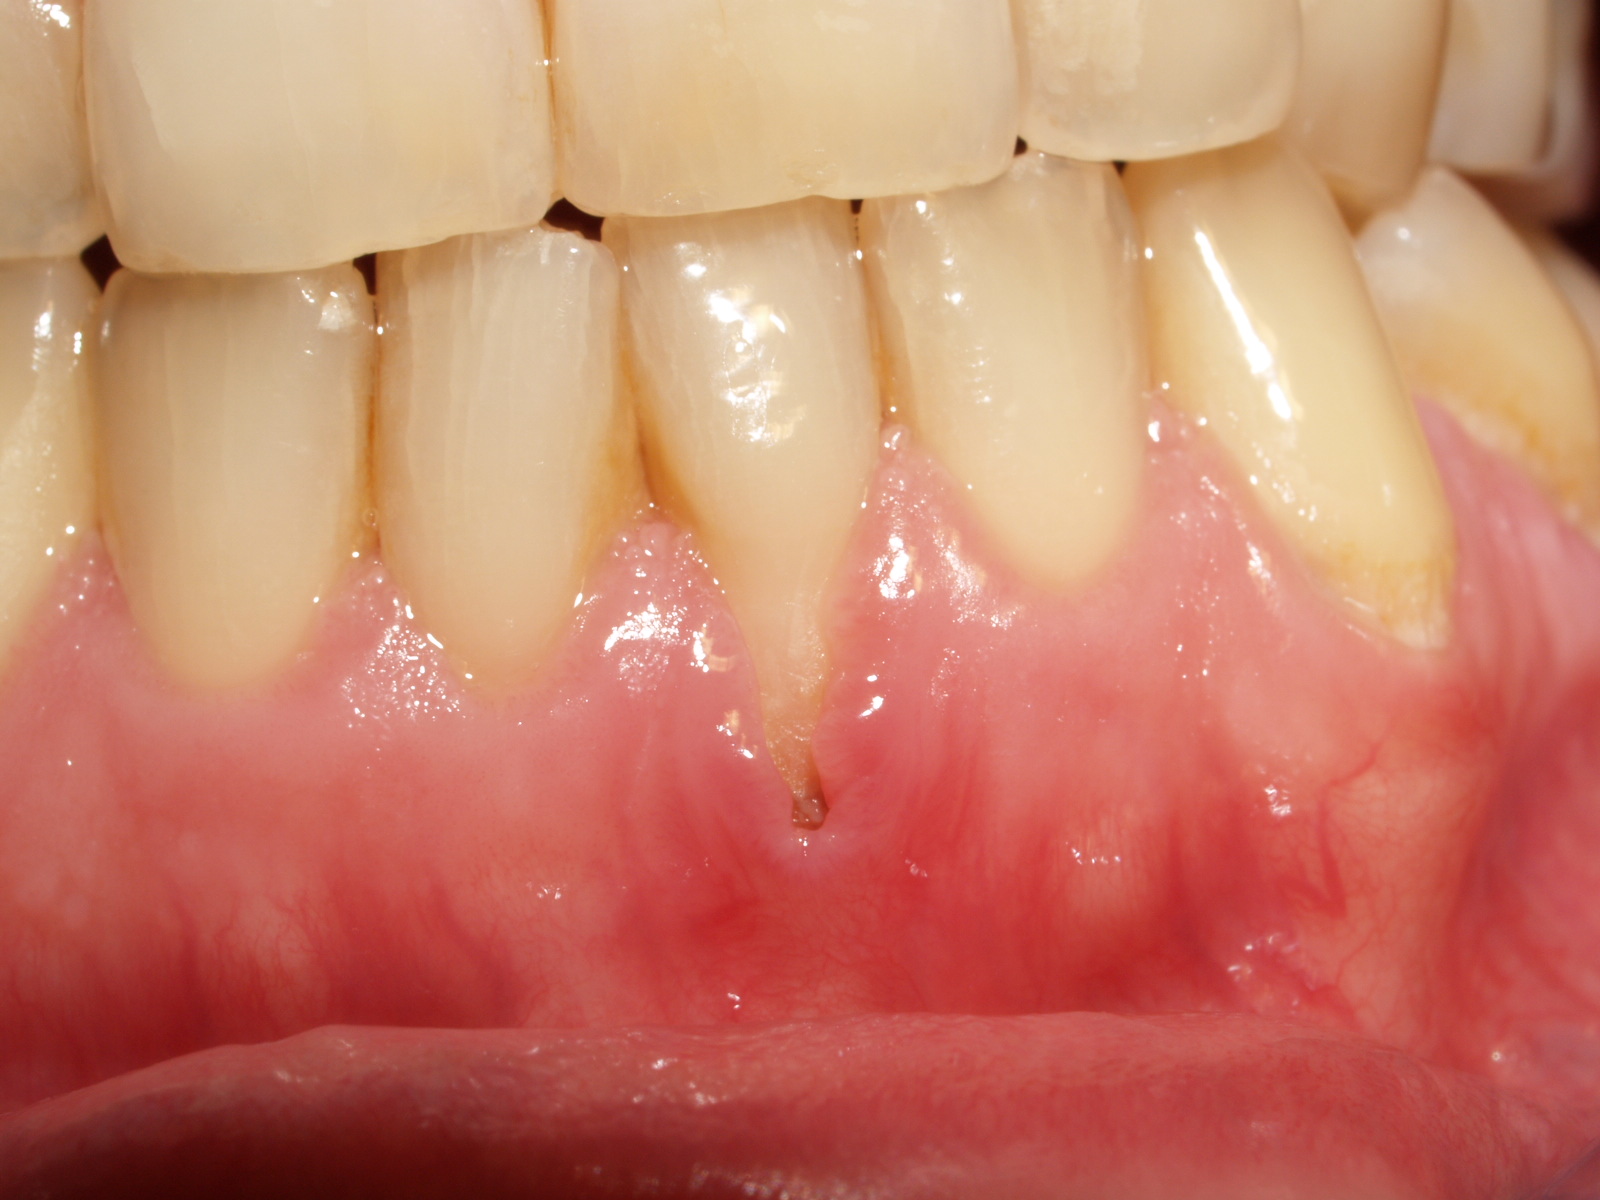

Pequeña Herida En La Encía, , , , , , , 0, Lesión en la encía, www.propdental.es, 1017 x 1024, jpeg, WebPor lo general, la causa de una herida en la encía suele ser un pequeño bocado, un cepillado demasiado frecuente o brusco, haber tomado algún alimento duro….. WebLas heridas en la encía se pueden desarrollar por razones diferentes como son las siguientes: La colocación de una prótesis mal ajustada. Cepillarse con mucha. Web1. Agua con sal – Es uno de los remedios caseros más populares y efectivos. Para eliminar la molestia en las encías, sólo bastará con calentar un poco de agua y añadirle sal.., 20, pequena-herida-en-la-encia, Novedades y Muebles WebPor lo general, la causa de una herida en la encía suele ser un pequeño bocado, un cepillado demasiado frecuente o brusco, haber tomado algún alimento duro….. WebLas heridas en la encía se pueden desarrollar por razones diferentes como son las siguientes: La colocación de una prótesis mal ajustada. Cepillarse con mucha. Web1. Agua con sal – Es uno de los remedios caseros más populares y efectivos. Para eliminar la molestia en las encías, sólo bastará con calentar un poco de agua y añadirle sal..

WebCuanto más pequeña sea la herida, más sencillo será su proceso de curación y menos molestias te causará. Si, por el contrario, observas que la llaga no remite con el paso de.

WebLas heridas en la boca y en los labios pueden surgir debido a aftas, golpes en la boca o irritación de la zona debido a alimentos muy calientes o fríos, por ejemplo. Asimismo, las. WebLas llagas pueden aparecer en prácticamente cualquier parte de la boca, siendo comunes en las encías y la cara interna de las mejillas, y existen muchas. WebUn punto negro en la encía de un bebé no suele tener su origen en la melanosis gingival. Lo más común es que se trate de un diente de leche. Si el diente. WebSi has notado la formación de un bulto en la encía detente a analizar tus síntomas. Por ejemplo, si el bulto está causando un dolor dental exacerbado es muy posible que se. WebLas encías sanas no sangran, por lo que si ves rastros de sangre al cepillarte los dientes o usar hilo dental, puede que sea un signo de que tus encías están. WebHerida en la encia. Hace varios meses ya eh tenido esta pepita blanca en la encía nunca me a dolido ni nada eh ido con periodoncia y odontología y dicen que a veces la encía. WebUn diente incluido está clavado en el tejido de la encía o en el hueso por varias causas. Puede ser que la zona simplemente esté apiñada y no exista el espacio. WebSi la herida en tu encía no cicatriza, lo mejor es que acudas a tu dentista. Es común que nos hagamos heridas en las encías al comer alimentos duros y/o puntiagudos..

WebUn diente incluido está clavado en el tejido de la encía o en el hueso por varias causas. Puede ser que la zona simplemente esté apiñada y no exista el espacio. WebSi la herida en tu encía no cicatriza, lo mejor es que acudas a tu dentista. Es común que nos hagamos heridas en las encías al comer alimentos duros y/o puntiagudos.. WebEne 2009 | 11.465 Mens. Herida en la encía y pequeña mancha en los incisivos inferiores. Pues eso shurmanos, ya llevaba días que me dolía la encía debajo.